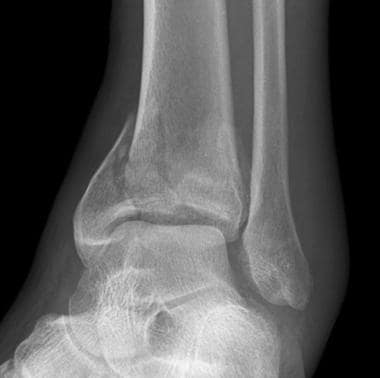

The ankle joint is a hinge type joint that resides at the distal part of the lower limb. It is formed by the talus (a bone of the foot), the lateral malleolus (bony end of the fibula on the outside of the ankle) and the medial malleolus (the bony end of the tibia on the inside of the ankle.